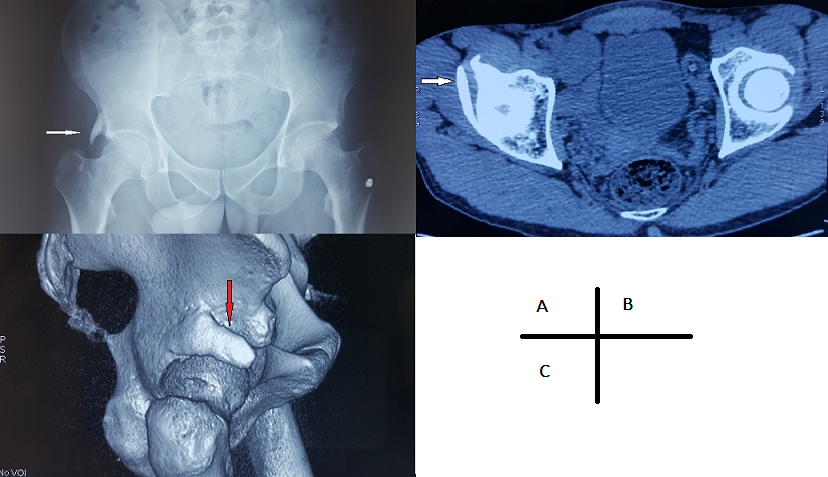

Le doigt pelvien est une anomalie anatomique rare caractérisée par le développement d’une structure osseuse dans les tissus mous adjacents au pelvis. Son origine est encore inconnue, mais la théorie suggère une anomalie apparaissant au stade mésenchymateux de la croissance osseuse au cours des six premières semaines d’embryogenèse. Nous présentons le cas d’un patient de 40 ans, grand sportif et qui consultait pour une douleur mécanique du pli inguinal droit survenue lors d’une séance d’entrainement. L’examen clinique trouvait une hanche droite douloureuse à la mobilisation mais sans limitation. Le reste de l’examen somatique était sans anomalies. La radiographie du bassin face a mis en évidence une protubérance osseuse en forme de doigt s’articulant avec l’angle supéro externe du toit du cotyle droit (A). La tomodensitométrie a montré le doigt pelvien, avec une corticale bien différenciée, s’articulant avec le toit du cotyle droit (B) et s’étendant en direction antéro-inférieure (C). Cette anomalie peut survenir à n’importe quel niveau des os pelviens, et peut même être localisée entièrement à l’intérieur des tissus mous de la paroi abdominale. La tomodensitométrie est utile dans ces cas car elle permet d’établir un diagnostic différentiel (tumeurs osseuses, ostéochondrome, myosite ossifiante et des fracture-avulsions du bassin). Occasionnellement, le doigt pelvien peut être bilatéral ou multiple. Il est généralement asymptomatique et de découverte fortuite. Il peut parfois être une source de douleur, de difficulté ou d’handicap fonctionnel à cause de sa proximité avec l’articulation. Dans ce cas, une excision chirurgicale peut être nécessaire.